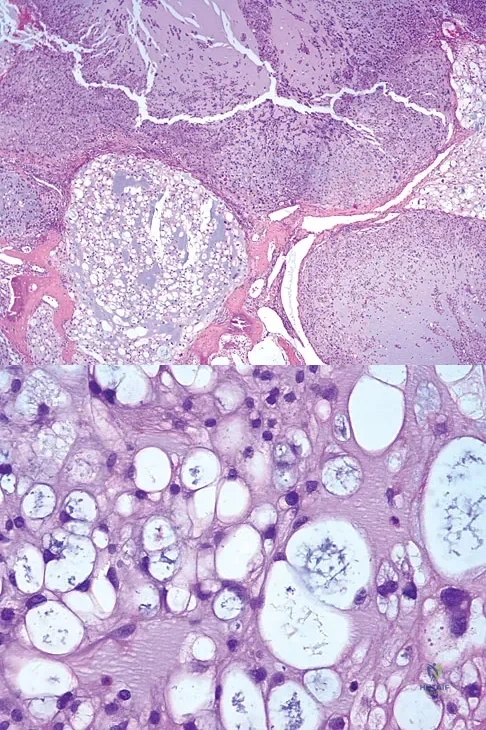

The biopsy specimens seen in Figures 55a and 55b are from a lytic lesion in the sacrum of a 58-year-old man. What is the most likely diagnosis?

Detailed Explanation